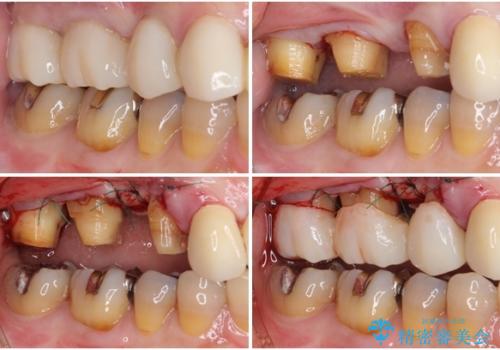

咬み合わせにより発現した歯周ポケットに汚れがたまり、歯周病のような状態になってしまっていました。

失われていた歯槽骨を、再生治療により可及的に改善させ、その1年後に歯周ポケットを除去するための歯周外科処置を行うこととしました。

歯槽骨の再生には1年ほどの待機期間を要し、その後のポケット除去処置も数か月の待機期間を必要とするため、治療期間は長期に及びました。

治療途中からマウスピースを装着していただくことで、歯槽骨の回復も順調に進みました。